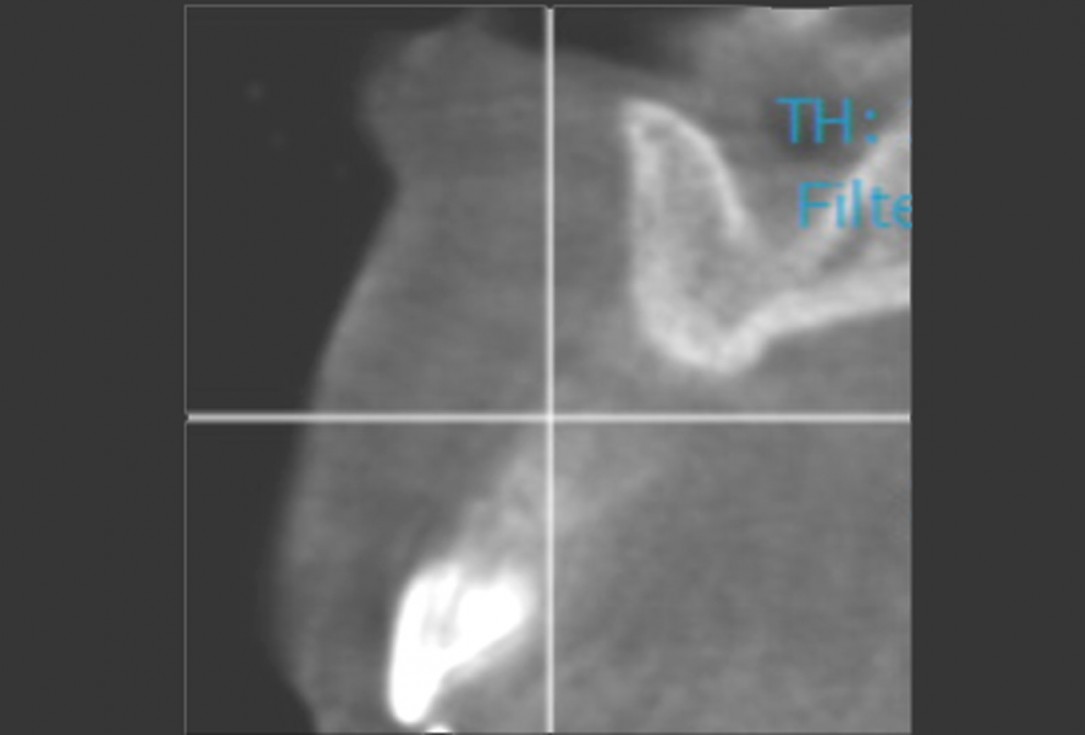

2/11 - CBCT scan pre-opmaxgraft® cortico at combined defect palatally and facially - Dr. K. Höckl

Pre-operative radiographic view.